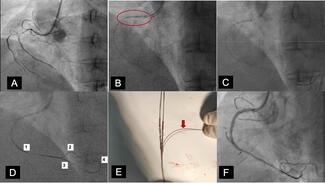

Basavanna Dinesh, MD, DM; Yamasandi Siddegowda Shrimanth, MD, DM; Aditha Cibi, MD; et al. Reprinted with permission from J INVASIVE CARDIOL 2024;36(8).